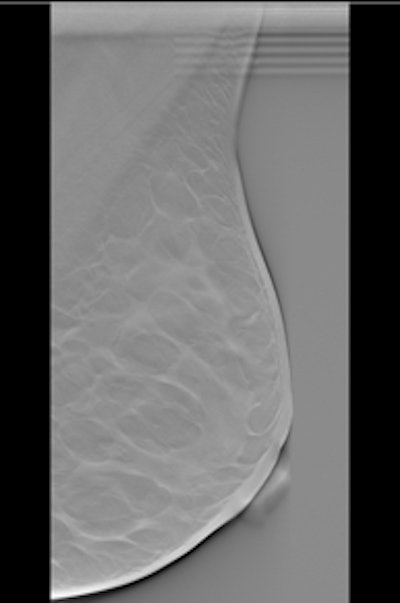

Left: Example of a breast tomosynthesis slice holding a simulated mass. Right: Example of a breast tomosynthesis slice holding a simulated microcalcification cluster. All images courtesy of Dr. Pontus Timberg.Image volumes can be viewed using free scroll volume browsing (FS) or in a cine loop. The standard procedure is FS, but in clinical practice observers often use a cine loop to get an overview of the images. In addition, breast tomosynthesis images may be displayed on the monitor in either vertical or horizontal orientation. The researchers evaluated the efficiency of several breast tomosynthesis image volume readings using an experimental setup. They assessed these in terms of lesion detection performance, time efficiency, visual attention, and search using jack-knife alternative free-response receiver operating characteristics (JAFROC) and eye tracking.

The researchers selected 55 normal breast tomosynthesis cases in mediolateral oblique view, which were then verified by an expert radiologist panel. The exams were acquired with a Siemens Mammomat Novation BT prototype (Siemens Healthcare). All viewing procedures consisted of FS, and three were combined with initial cine loops at three different frame rates (9, 14, and 25 fps). The presentation modes consisted of vertically and horizontally orientated image volumes.